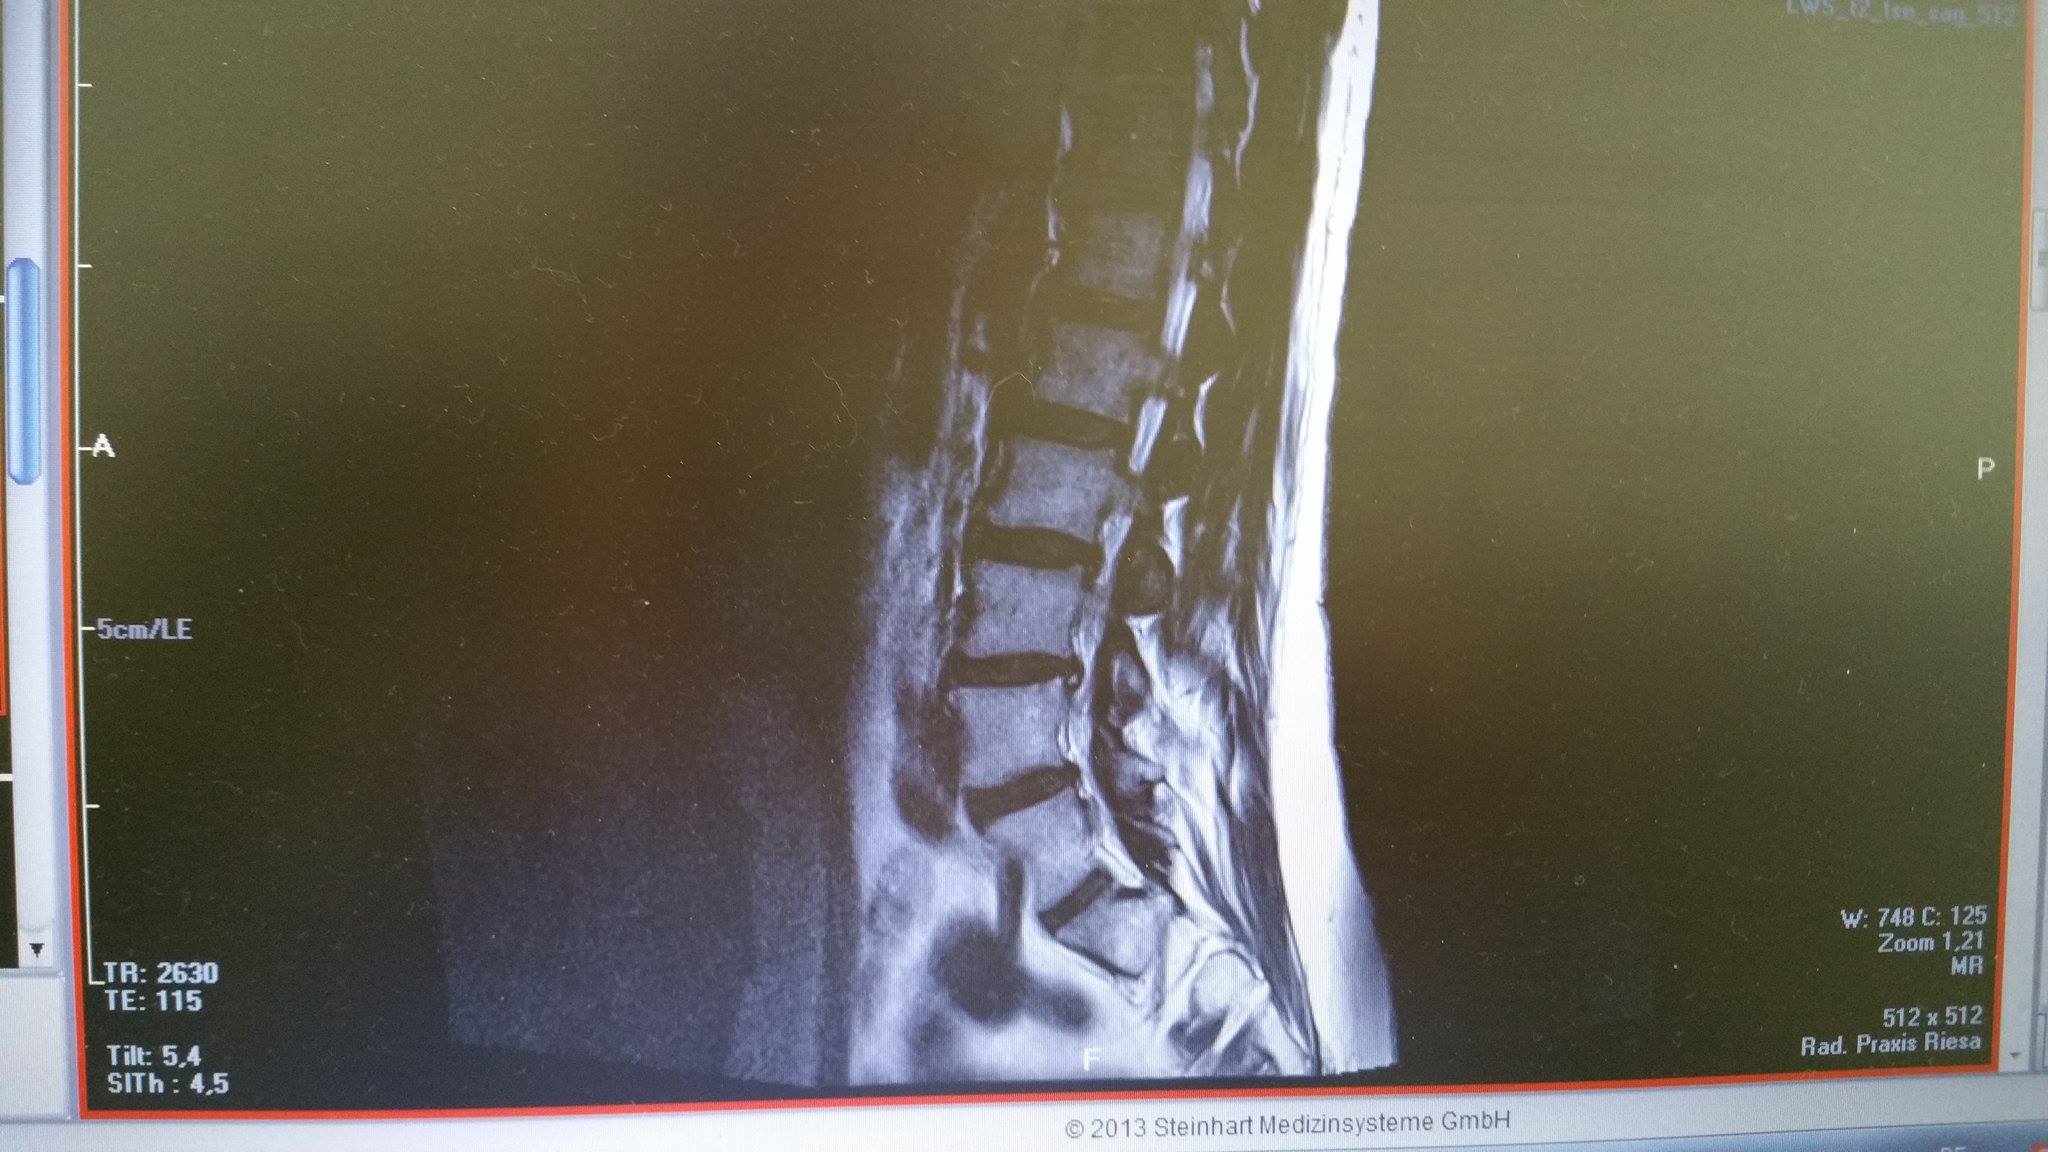

Daraus können schließlich die MRT Bilder (Schnittbilder) erzeugt werden. Dadurch entstehen verschieden aussehende Bilder. ▶ MRT in Oberhausen Kontaktdaten ⏲ Öffnungszeiten Bewertungen Das Telefonbuch Ihre. Leider ist alles unverändert bzw. schlimmer geworden.

Leider ist alles unverändert bzw. schlimmer geworden.